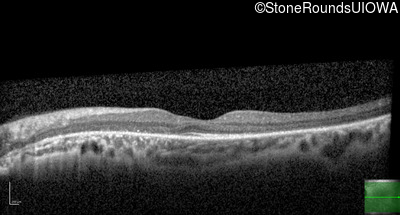

Optical Coherence Tomography - Right - 20/100

Exemplar / OCT Stack

OCT Stack